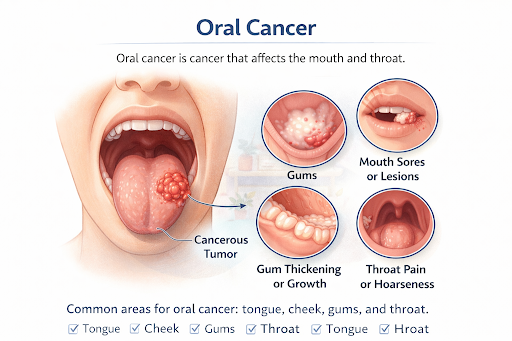

Overview Of Oral Cancer

Oral cancer is a type of head and neck cancer that develops in the tissues of the mouth and oral cavity. It most commonly arises from squamous cells, which form the protective lining of the lips, tongue, gums, cheeks, and floor of the mouth.

In its early stages, oral cancer may appear as a small, painless ulcer, sore, or discolored patch, often ignored or mistaken for a minor oral issue. Without timely diagnosis and treatment, these abnormal cells can grow and spread to nearby tissues.

When detected early, oral cancer has significantly better survival rates and improved long-term quality of life, making awareness and regular screening crucial.

In its early stages, oral cancer may appear as a small, painless ulcer, sore, or discolored patch, often ignored or mistaken for a minor oral issue. Without timely diagnosis and treatment, these abnormal cells can grow and spread to nearby tissues.

When detected early, oral cancer has significantly better survival rates and improved long-term quality of life, making awareness and regular screening crucial.

Where Oral Cancer Begins

Oral cancer can affect multiple areas within the mouth, including:

- Lips – impacting facial movement and speech

- Tongue – affecting taste, speech clarity, and swallowing

- Gums – leading to oral discomfort and loosening of teeth

- Inner cheeks (buccal mucosa) – causing pain and restricted mouth opening

- Floor of the mouth – interfering with tongue movement and swallowing

- Roof of the mouth (palate) – affecting chewing and speech resonance

- Salivary glands – reducing saliva production and causing dry mouth

Effect of Oral Cancer on Daily Oral Functions

As oral cancer progresses, it may lead to:

- Difficulty chewing and swallowing food

- Changes in speech or voice clarity

- Reduced tongue movement and loss of taste

- Persistent mouth pain, numbness, or burning sensation

- Excessive drooling or dry mouth

- Poor oral hygiene and increased risk of infections